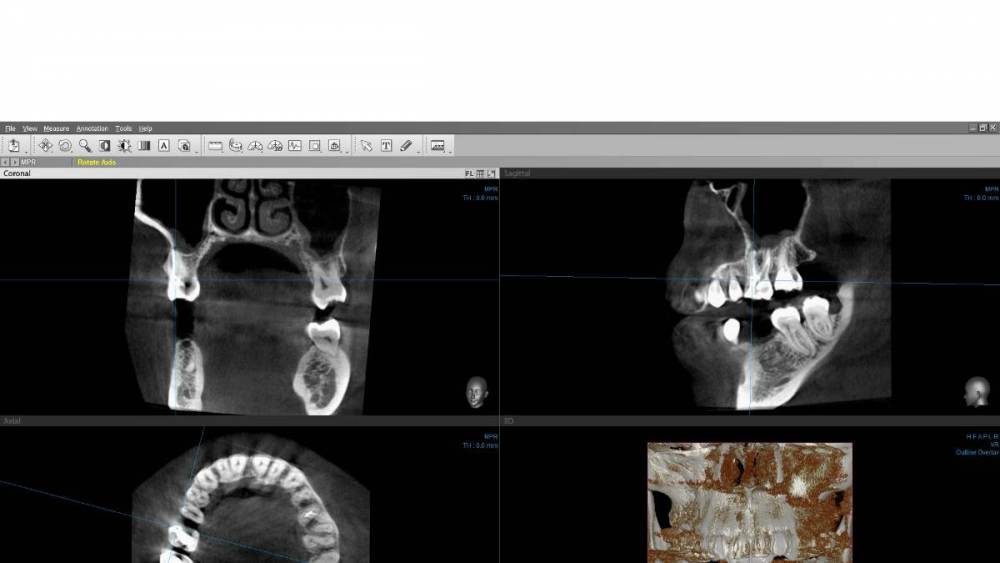

Mariaduya Опубликовано 5 июля, 2023 Поделиться Опубликовано 5 июля, 2023 (изменено) Здравствуйте. У меня сложная ситуация, боли в челюсти практически 1.5 года. Врачи не видят проблем, уже не знаю куда обратиться. Хронология. 1. В ноябре 2021 начал слегка болеть 1.6 зуб. В стоматологии мне его сразу начали депульпировать, без снимка. В ходе лечения не болел, как запломбировали каналы, постепенно появилась ноющая, постоянная боль. Я обратилась снова, сказали, что на зубе есть хроническое воспаление и ввели антибиотик туда при помощи электрофареза. Среагировал 2.5 зуб с другой стороны, и тоже начал постоянно болеть, он был депульпирован давно, но в нем развился большой кариес. 2. Мне начали их перелечивать. 1.6. не получилось пройти канал, залили резодентом, 2.5 просто переличили. 3. Боль все ещё осталась, уже в двух зубах. Врачи ничего не знают, отправили к неврологу, ЛОРУ и т.д. 4. Обошла неврологов, лоров, делала мрт, кт с контрастом головы, пазух носа, все ок. Невролог выписывает финлепсин, не помог. 5. Делала в частной клинике кт зубов, без описания, ещё не знала, что оно нужно, врач посмотрела и сказала, что видит небольшое, хроническое воспаление на 1.6 зубе и все, а так она не знает. 6. И так 1.5 года никто не знает, что со мной. Боль 1.6 и 2.5 зубы, начинают и нижние зубы болеть, уже и ухо болит. После орви болит все очень сильно, что хочется уже не просыпаться. Удалять их говорят не показаний, вдруг боль останется. Снимки в хронологии выкладываю. Есть ли на них воспаление 1.6 зуба, 2.5 зубов, есть ли них кисты свищи и все что угодно, что аномально и может вызывать боль. Может что-то с надкостницой, или суставами. Все что у меня есть - интернет, так как живу я очень далеко от нормального города и доступна только городская поликлиника, где врачи говорят, что это неврология, а невролог говорит наоборот. Сами зубы болят странно, по очереди. Если болит неделю 1.6 зуб, то 2.5 не болит и так наоборот. Вместе они не болят. Ещё странное то, что они практически симметричны друг другу по расположению. Изменено 5 июля, 2023 пользователем Mariaduya Ссылка на комментарий

Carioznik Опубликовано 10 июля, 2023 Поделиться Опубликовано 10 июля, 2023 (изменено) образ диска с Вашим КТ - не открывается (поврежден). Либо создан с ошибкой, либо не загрузился нормально. Можно просто все папки на диске заархивировать и закачать. Хотя, думаю, уже пора новое КТ делать и разбираться на его основе. Изменено 10 июля, 2023 пользователем Carioznik Ссылка на комментарий

Carioznik Опубликовано 13 июля, 2023 Поделиться Опубликовано 13 июля, 2023 по этому старому КТ: на 16 - есть пропущенный канал, от этого, на одном из корней - есть небольшой воспалительный процесс (на тот момент). "Само не заживет", будет только расти, может, на сегодняшний момент - уже стал большой). Но жалобы в таких случаях обычно другие. Делайте новое КТ (по старому только гадать...) и снова, очный осмотр стоматолога, явно понадобится. 1 Ссылка на комментарий